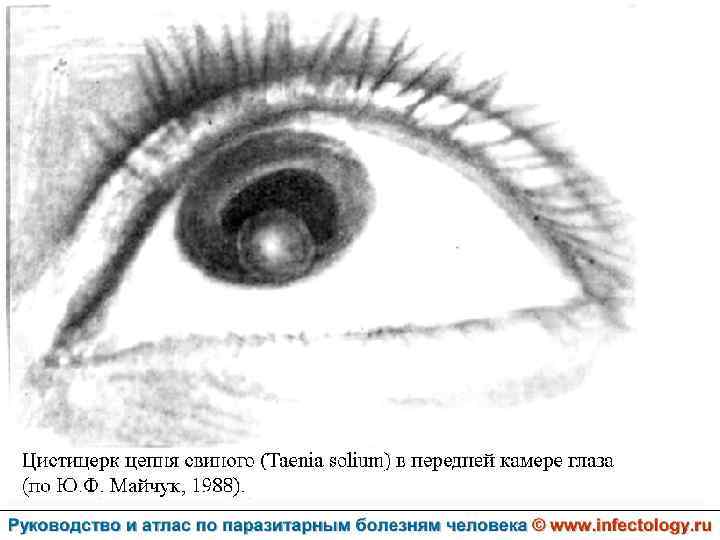

Цистицеркоз (шифр по МКБ 10 - B 69) – биогельминтоз, который вызывается паразитированием в тканях и органах человека и животных личиночной стадии цепня вооруженного – цистицерка (Cysticercus cellulosae) Болезнь проявляется разнообразными симптомами в зависимости от локализации цистицерков.